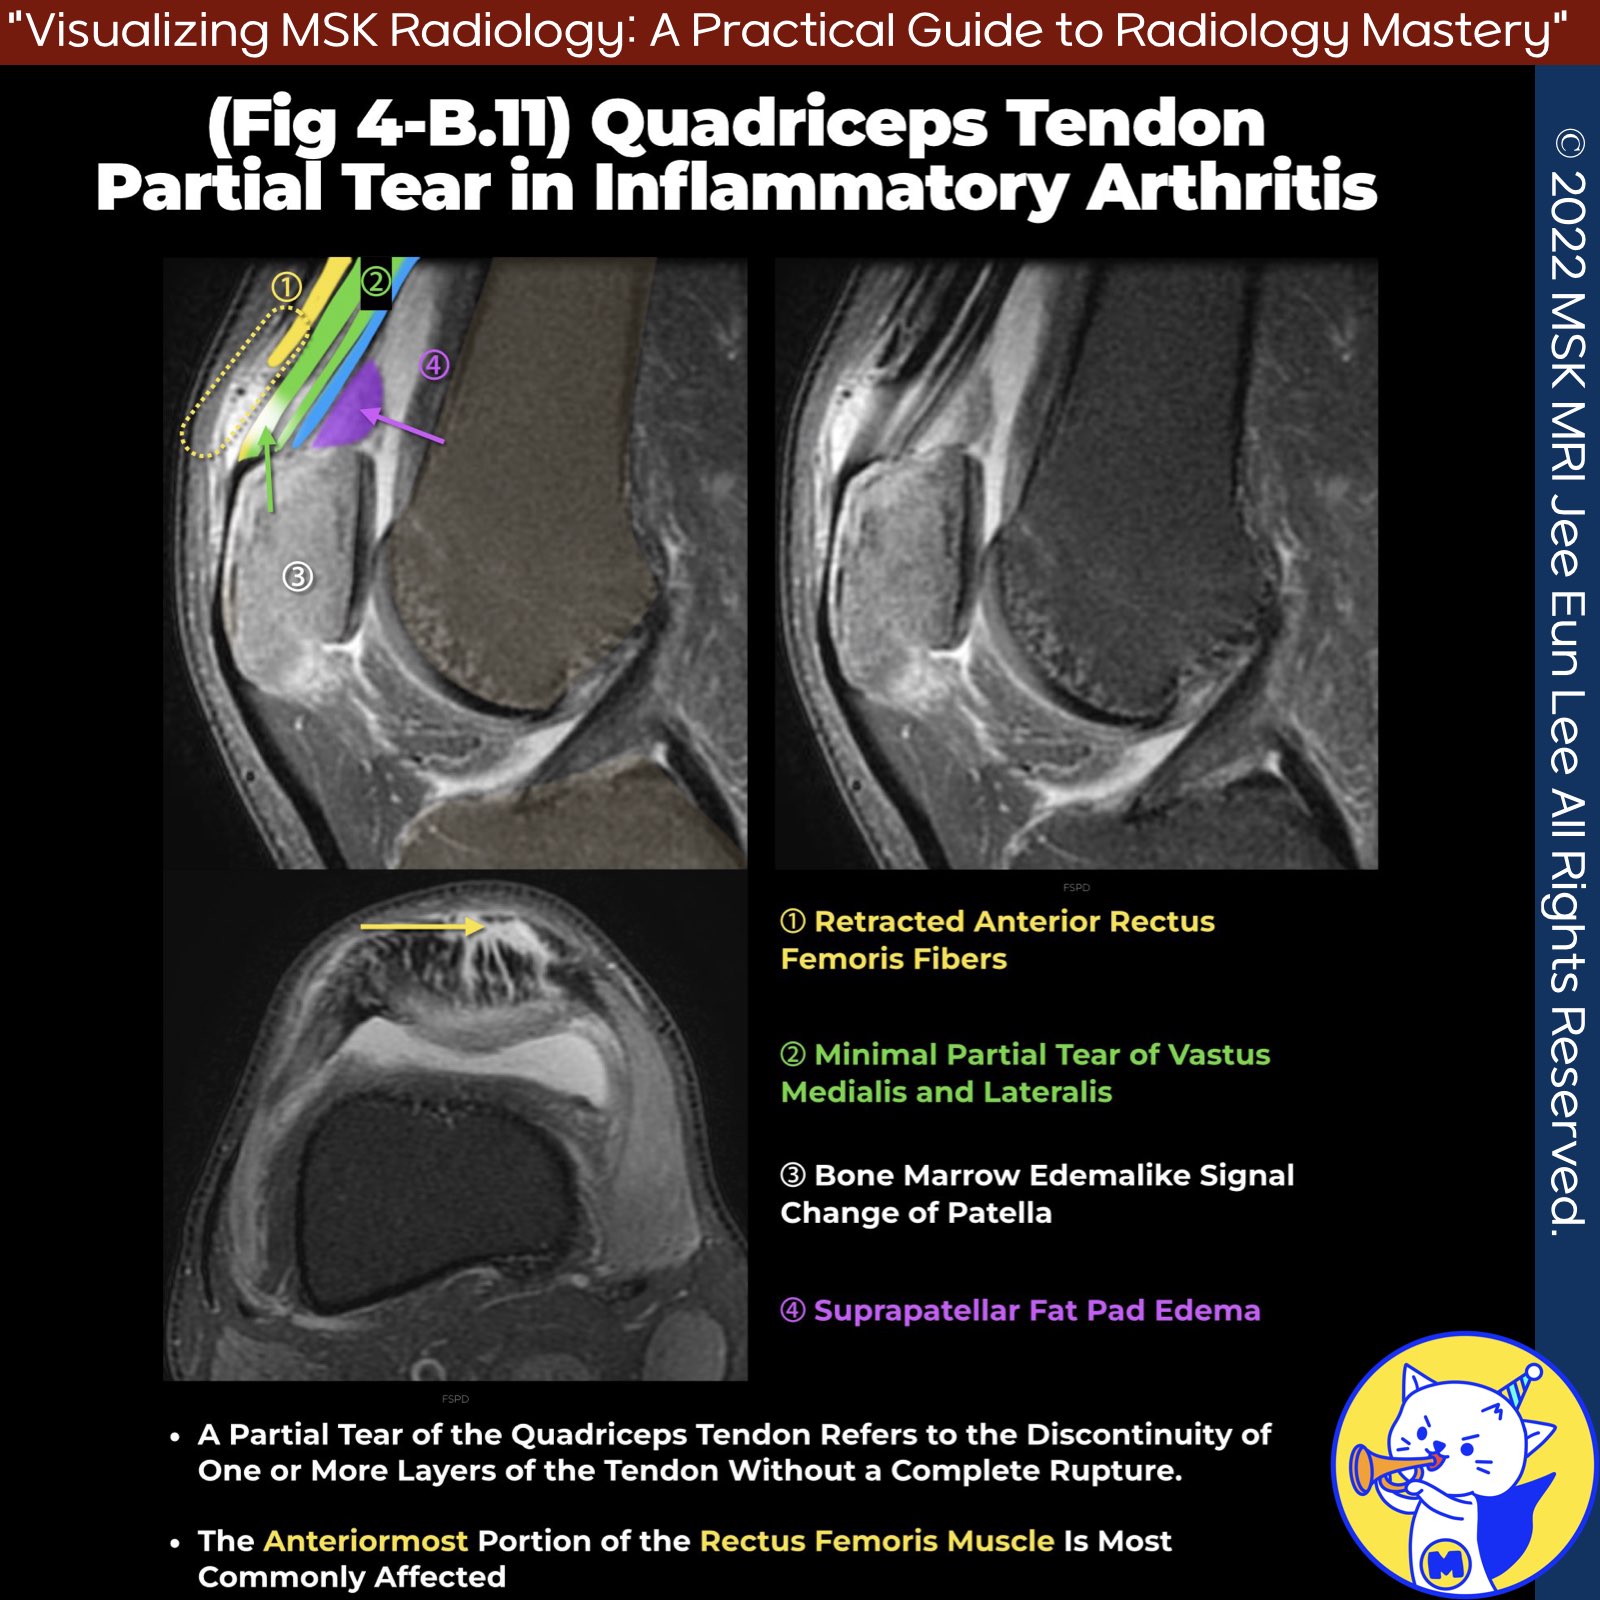

3️⃣ Partial Tears

- May be limited to the anterior, central, and/or posterior laminae, most commonly affecting the anterior rectus femoris portion

- Produce anterior soft-tissue swelling and bruising, may be associated with a palpable gap

- Torn rectus femoris tendon can retract far proximally, often overlooked at dedicated knee MRI examination

- Less common and more challenging to identify clinically, seen at imaging as defects in the tendon filled with fluid

- Function is typically preserved and can be managed conservatively

✅ Atraumatic Tears

- Associated with systemic disorders such as hyperlipidemia, thyroid dysfunction, chronic renal failure, rheumatoid arthritis, corticosteroid use, gout, and diabetes

- May be bilateral